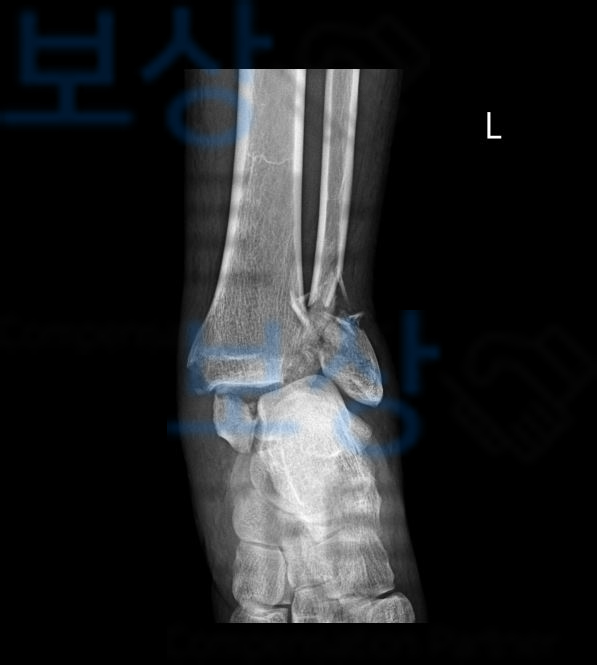

이 사고로 의뢰인은

족관절 골절 탈구 s82820 족관절 양과 골절 s930 진단받아 초기 금속외고정을 시행하셨고 이후 금속내고정술로 골절된 골편을 정복하는 수술을 받으셨죠 발목 골절 수술을 2차례 받으셨습니다.

발목 골절 중 양과골절은 발목 관절을 3개의 뼈중 2개의 뼈인** 경골(Tibia)과 비골(Fibula)**의 하단이 골절된 것입니다.

양과골절 즉 발목골절은 뼈와 관절을 이루고 있는 관절면이 함께 손상되는 경우가 많기 때문에 부러진 뼈를 제자리에 맞추는 정확한 정복이 이루어지지 않을 경우 수술하고 골유합이 잘 되었다 해도 외상성 관절염이 발생할 수 있습니다.